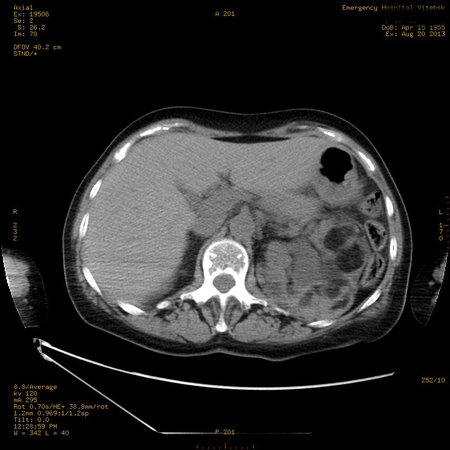

УЗИ почек - туберозный склероз

Пожилая женщина с нормальными мочевиной и креатинином.

Ангиомиолипоматоз почек , думаю компонент туберозного склероза.

Да, туберозный склероз.

Случай консультирован на кафедре радиологии Католического университета г.Лёвен (Бельгия) - зав каф. профессор Р.Оуен.